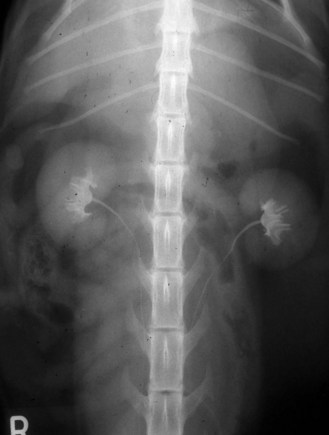

Procedure: Intravenous urography for examination of the kidneys and ureters (Fig. 6.23):

Figure 6.23 Use of water soluble iodine to highlight the urinary tract – taken 5 minutes after i.v. administration.

7. Action: Bolus administration: using 300–400 mg iodine/ml conc. at a dose of 850 mg/kg body weight (approximately 1 ml/kg). Administer as rapidly as possible and take radiographs as soon as the injection is completed. Take serial radiographs at 1, 5, 10, 15 and 20 minutes.

Rationale: The iodine is excreted by the kidneys and will appear within the renal parenchyma within a few minutes (Fig. 6.23). Opacity increases as the process continues and iodine enters the bladder.

8. Action: Infusion administration: using 150–200 mg/ml iodine concentration at a dose of 1200 mg/kg body weight (approx. 8 ml/kg); may be diluted with dextrose or saline and given via an intravenous catheter over a period of 10–15 minutes. Take radiographs at 5, 10 and 15 minutes after the start of the infusion. Both VD and lateral views can be taken.

Rationale: The iodine is excreted by the kidneys and will appear within the renal parenchyma within a few minutes. Opacity increases as the process continues and iodine enters the bladder.